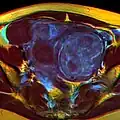

MRI image with multiple uterine leiomyomas -